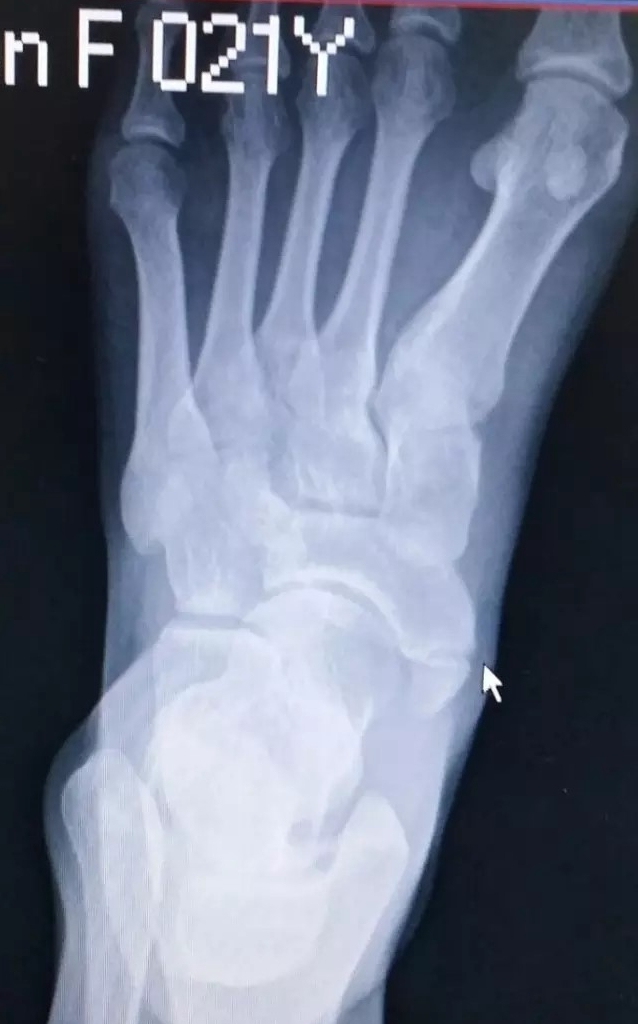

副舟骨损伤多见于青壮年男性,常见发生在足内翻崴脚扭伤后。此时胫骨后肌突然收缩或将在副舟骨上的附着点撕脱。

当发生足副舟骨疼痛时,首先要拍X光确诊,并确定分型。

没有撕脱位移可以保守治疗,使用足弓垫支撑足弓缓解症状。

发生撕脱位移可以膝下行石膏固定,症状严重的应该考虑手术治疗。